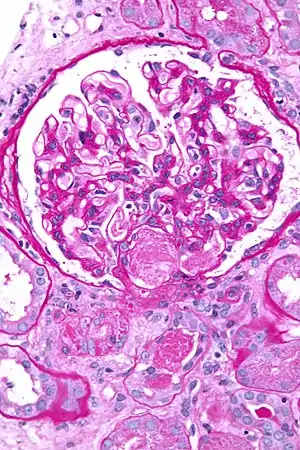

| عکاسی ریزنگاری showing an acute thrombotic microangiopathy, the histologic correlate of DIC, in a kidney biopsy. A ترومبوز is present in the hilum of the گلومرول (center of image). PAS stain. | |